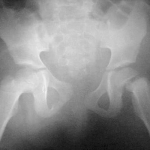

Caracterización de las fracturas por fragilidad previas a una fractura de cadera. Estudio retrospectivo de 200 casos

Nadia Gabotto Loredo, Gonzalo M. Viollaz, Lucio Gutiérrez, Joaquín Swinnen, Germán Garabano, Melina Saban, Álvaro J. Muratore, Diego J. Gómez, Alejandro Tedeschi, Gustavo J. Teruya